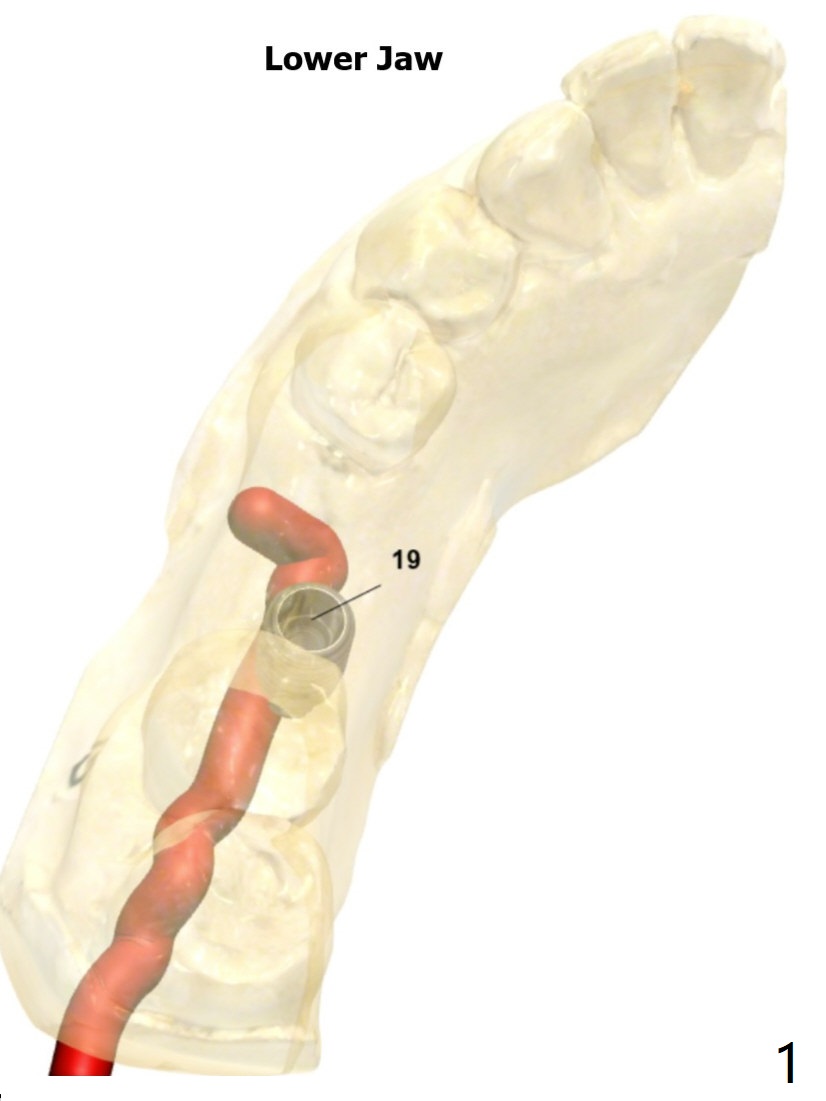

Buccal Plate Collapse: Lingual Placement

Return to Lower Molar Immediate Implant, Trajectory II